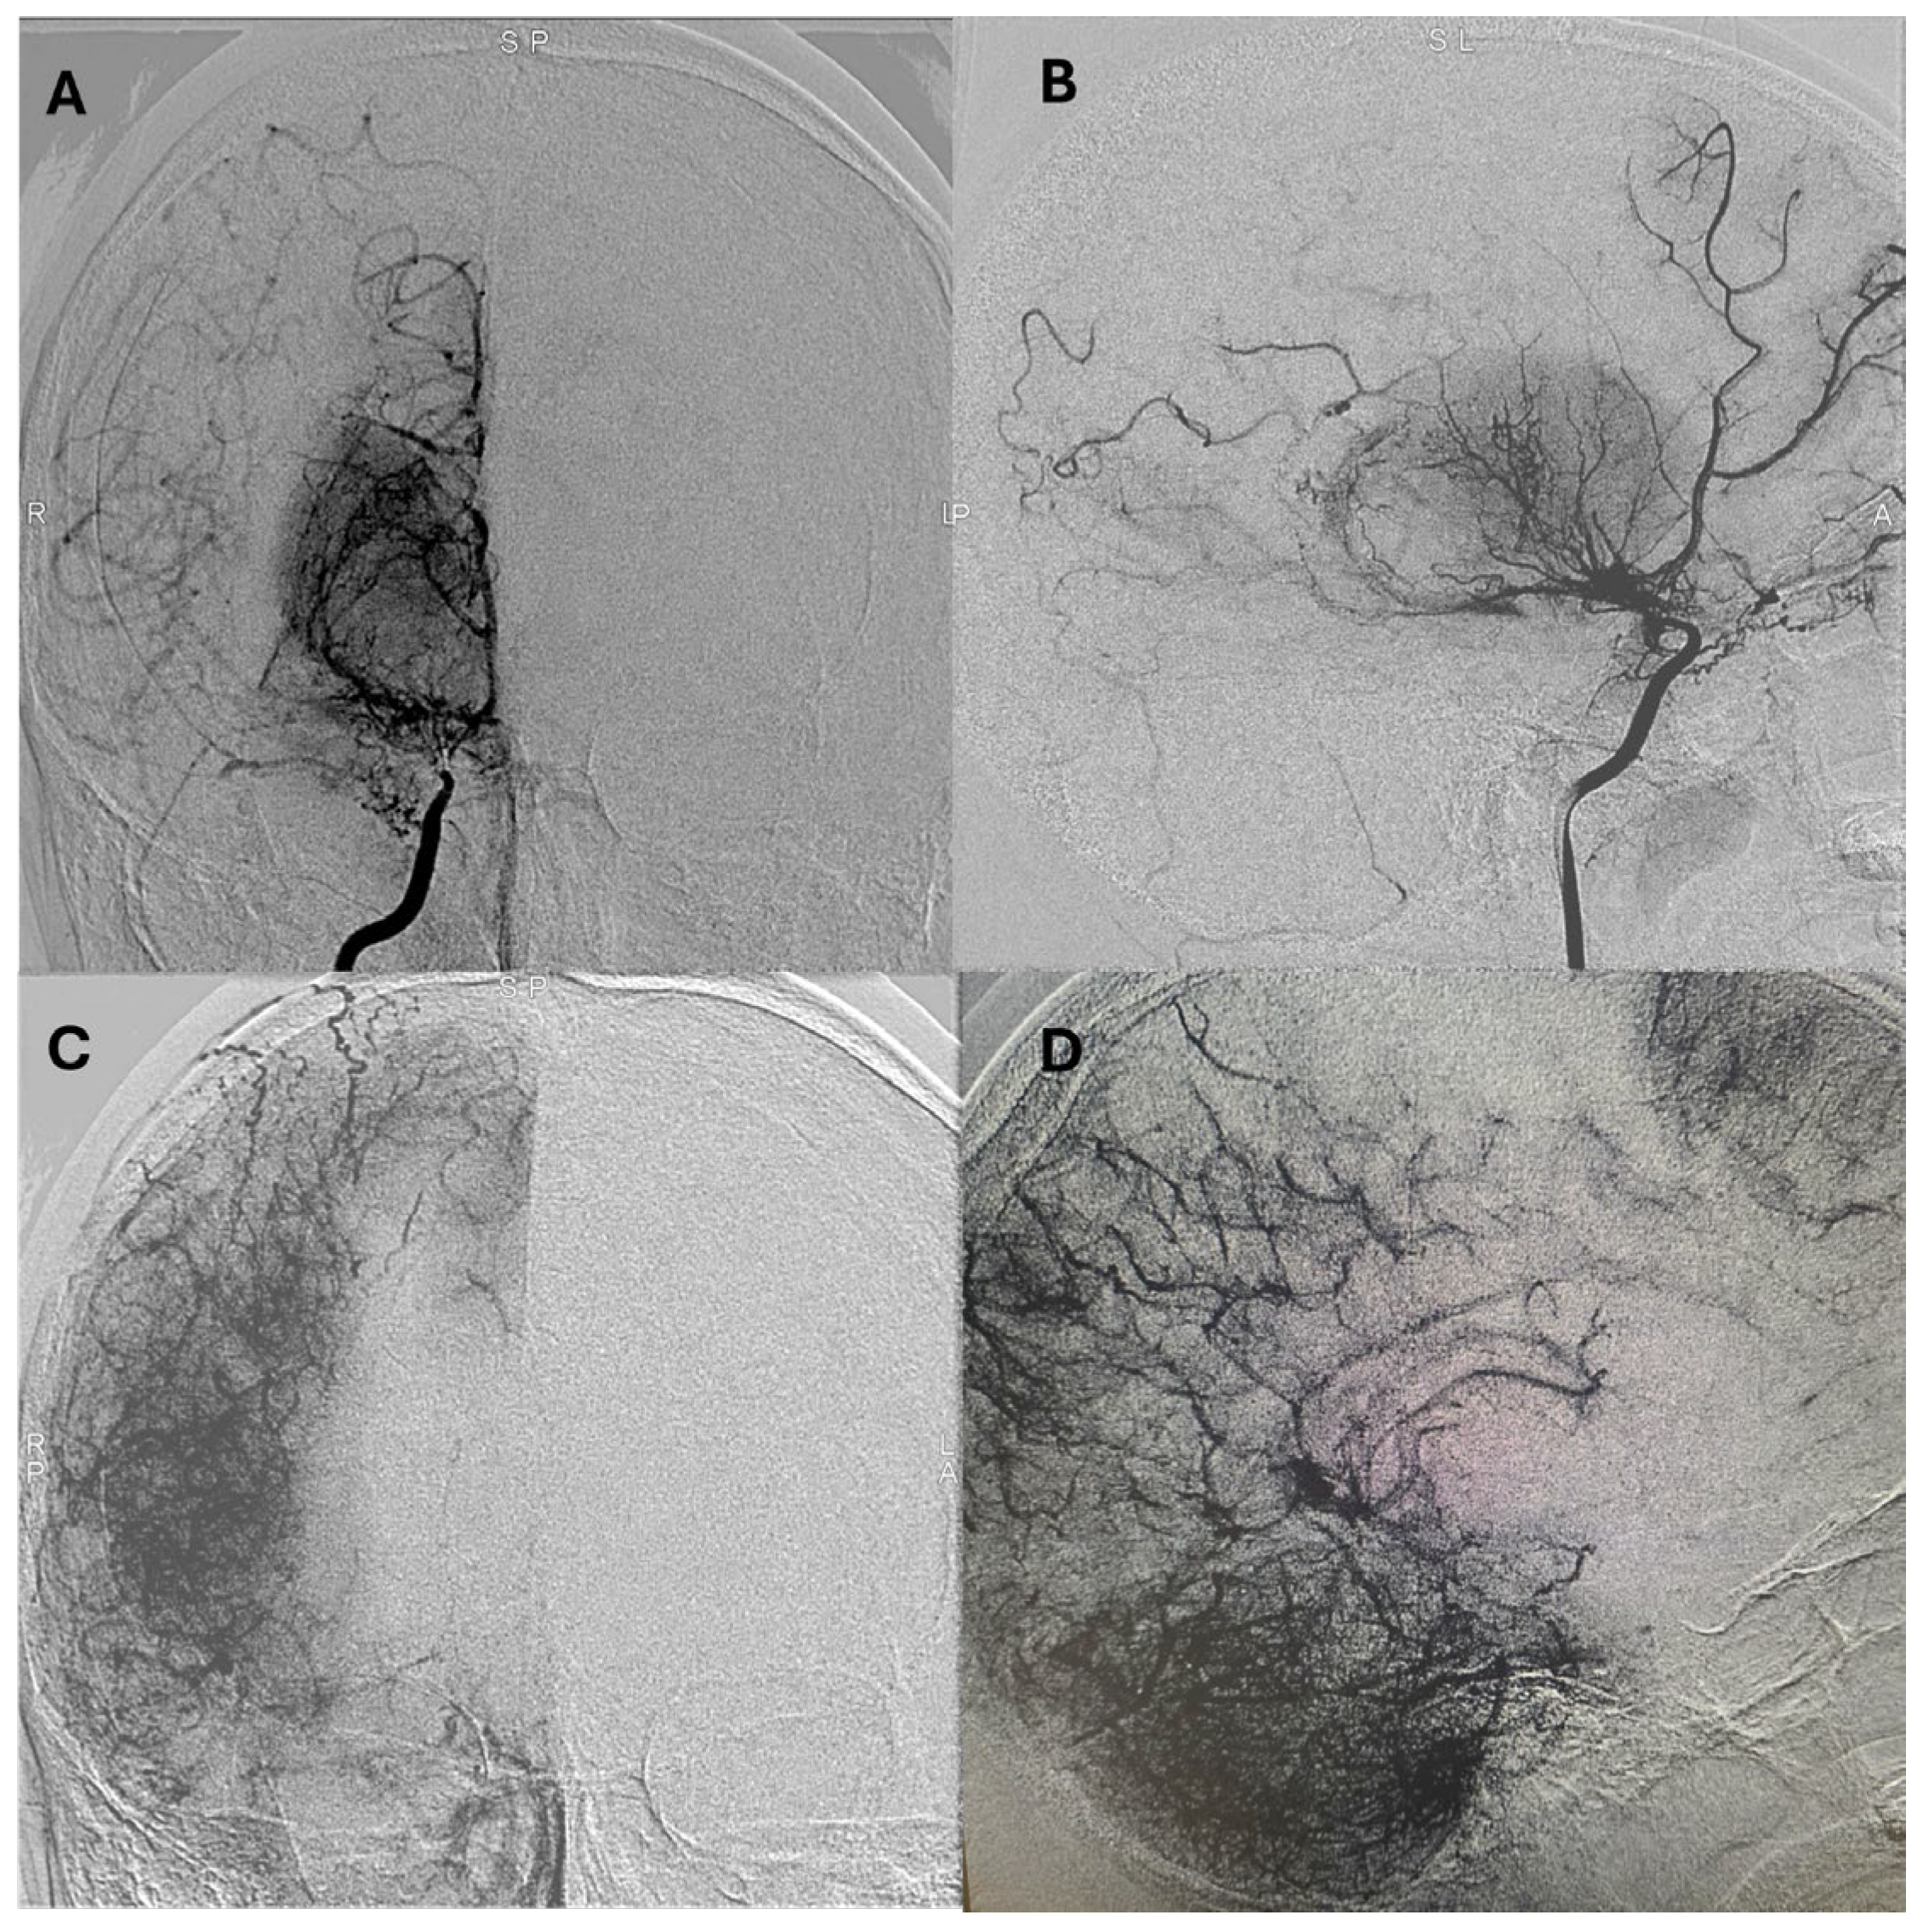

Representative postoperative angiographic images are shown in

Figure 1,

Figure 2 and

Figure 3. The mean operative time was 3.2 h and the average length of hospital stay was 7 days. All patients were monitored in the pediatric intensive care unit for 24–48 h before being transferred to the ward.